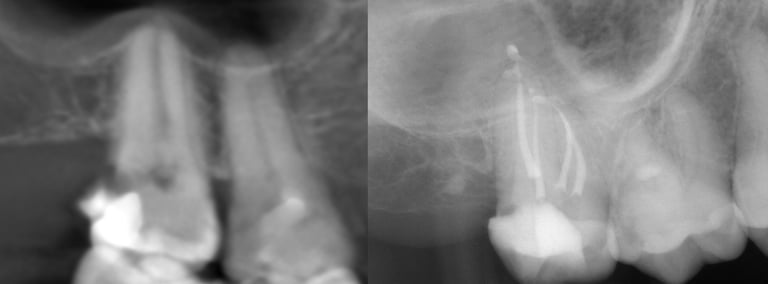

Gallery 1: Initial Cases

Initial Root Canal Cases with preoperative and postoperative radiographs.

#2 RCT with 4 canals

#19 RCT with 4 canals